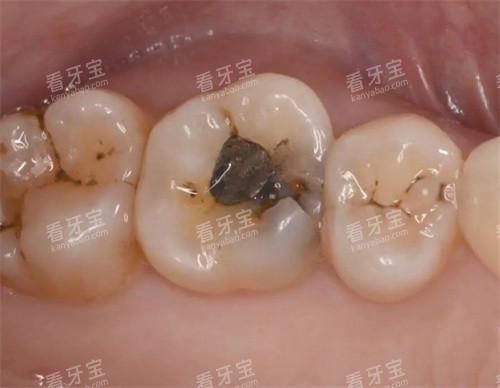

树脂补牙:200元起(前牙美学修复加收30%)

根管治疗:800元/颗起